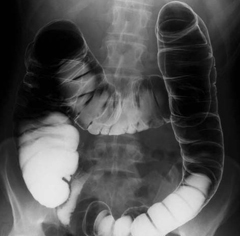

Само исследование выполняют следующим образом: под рентгенологическим контролем толстую кишку постепенно заполняют взвесью и производят прицельные и обзорные снимки всех ее отделов в различных положениях больного (лежа на спине, на боку, на животе). После чего делают еще два обзорных снимка: 1 – после полного распределения бария, он позволяет оценить диаметр просвета, форму и расположение толстого кишечника; 2 – после извлечения трубки и опорожнения кишечника, чтобы исследовать рельеф слизистой оболочки и определить функциональную активность органа.

И на последнем этапе выполняют технику двойного контрастирования. И если для предыдущей процедуры можно было использовать обычную клизму, то эту выполняют только устройством для ирригоскопии. Для этого аппаратом кишку дозировано заполняют воздухом. Слизистая еще покрыта тонким слоем контраста, а воздух расправляет складки, что дает возможность более детально изучить структуру стенки. Именно метод двойного контрастирования – определяющий при диагностике язв, полипов и онкологических процессов в толстой кишке.